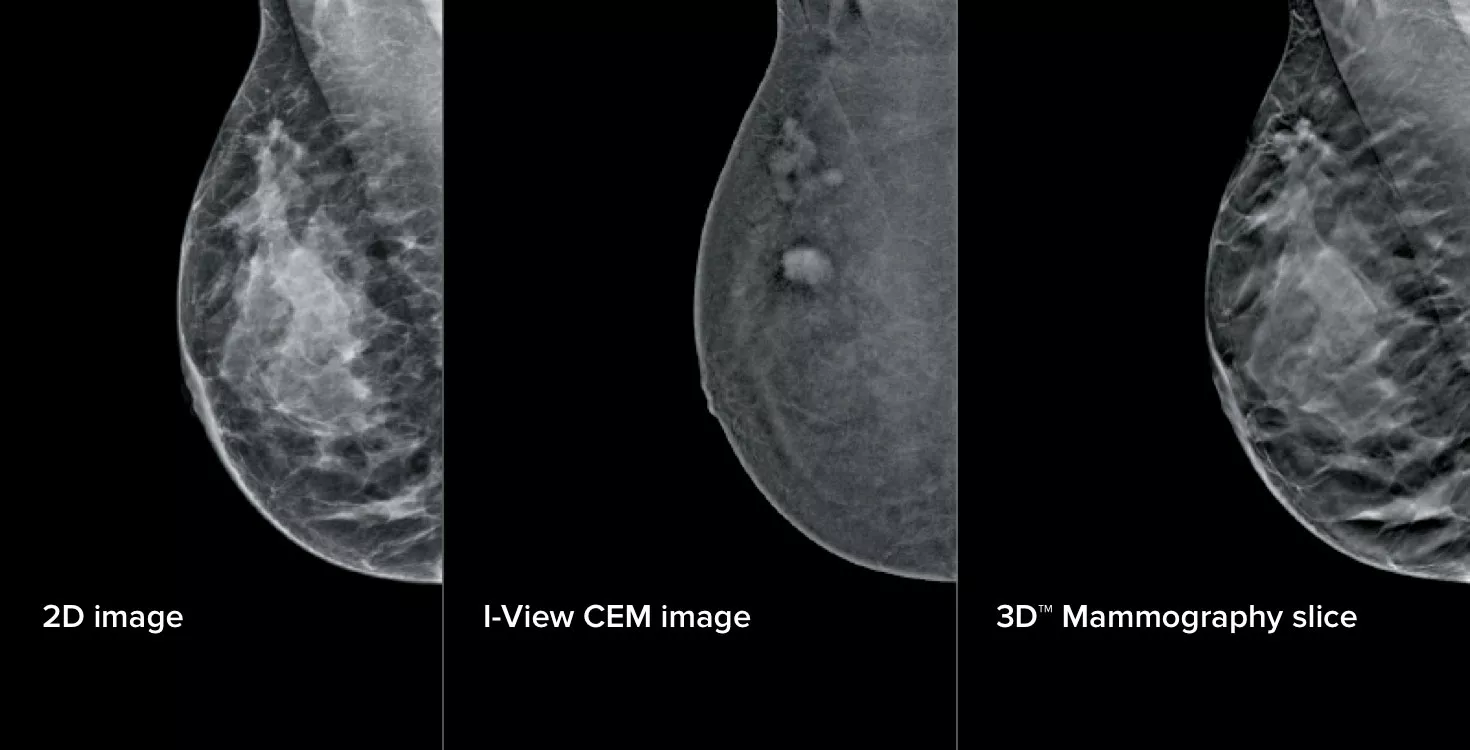

Kontrastforbedret mammografi (CEM) – billeddannelse af et bryst ved hjælp af jodholdig kontrast for at afsløre områder med øget blodforsyning i brystet – kan bidrage til at fremhæve mistænkelige læsioner. I-View-softwaren kan kombinere styrken i CEM med 2D- og tomosyntesebilleder, alt sammen under én kompression, hvilket giver anatomisk og funktionel billeddannelse i én undersøgelse.1

Denne software registrerer både anatomiske og funktionelle oplysninger i en enkelt undersøgelse ved at udnytte vores evne til at levere 2D-, kontrast- og tomosyntesebilleder i blot én kompression.1